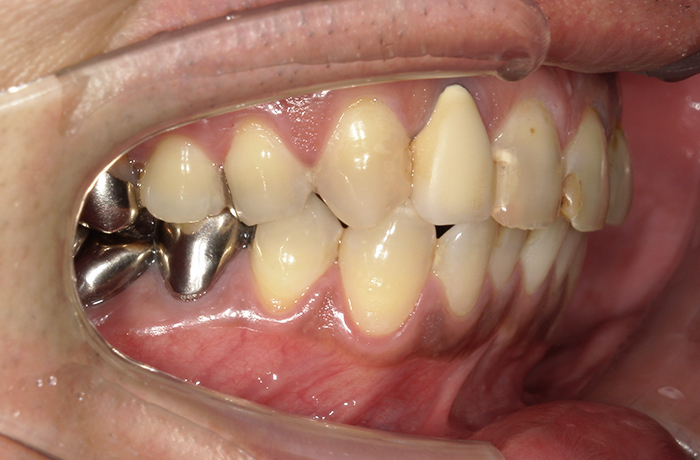

治療前

口腔内写真とレントゲン写真

右上2番は骨吸収が進み、動揺と咬合痛を伴っていました。

保存困難な状態であり、審美的にも歯頚ライン(歯の見えている部分と歯肉や顎骨に埋まっている部分の境界)の不調和が見られました。